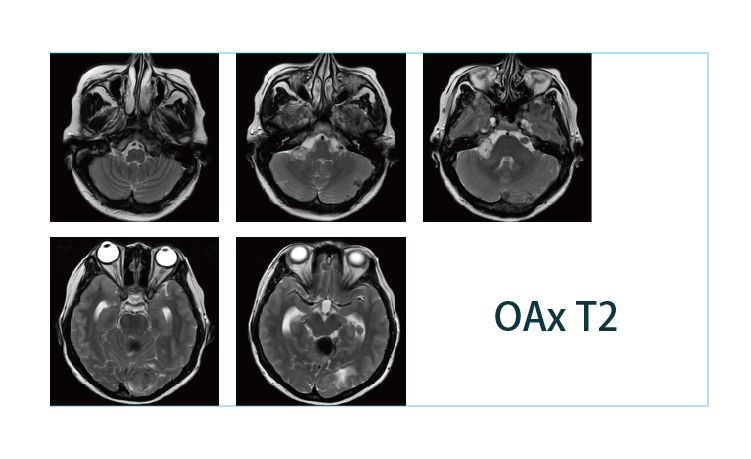

【朗润影像档案】20190412磁共振影像病例结果讨论